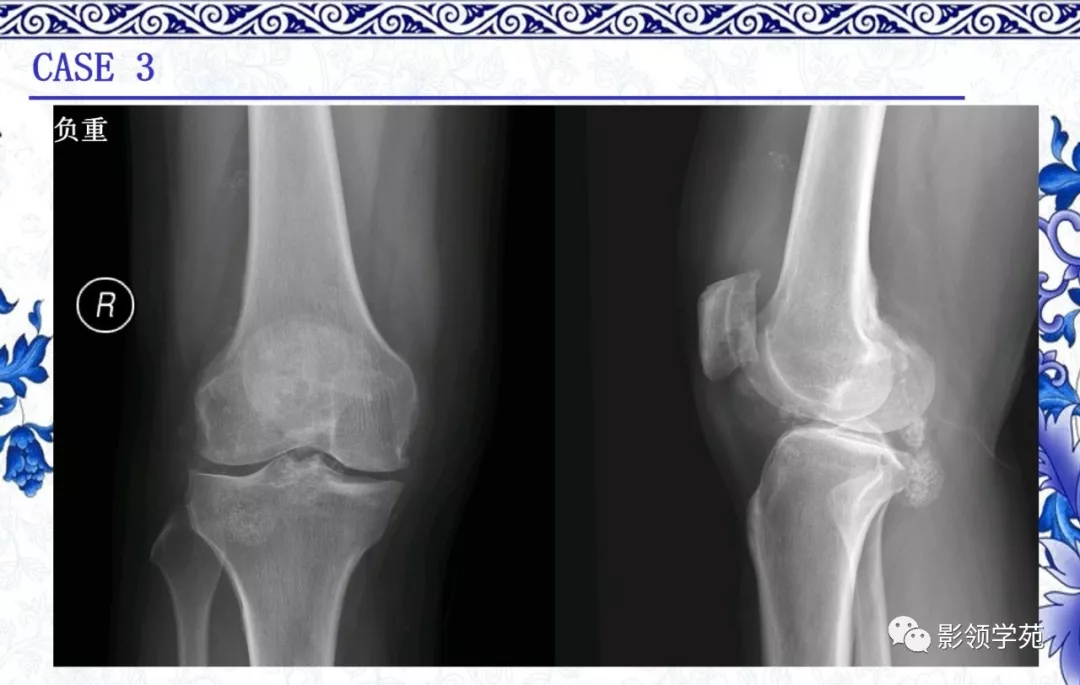

内生软骨瘤

· 良性肿瘤

· 多见于10-50岁

· 最常见于手部短管骨,长管骨多见于肱骨近端、胫骨远端、股骨近端及远端髓腔内

· 影像表现:

1. 多呈分叶状,边界清楚,缺乏硬化

2. 钙化程度不一,呈典型的点状、环状和弧形

3.中心型居多,可见膨胀或骨内膜扇贝样改变

4.非矿化区密度近似水,T2WI高信号,可见低信号钙化及分隔